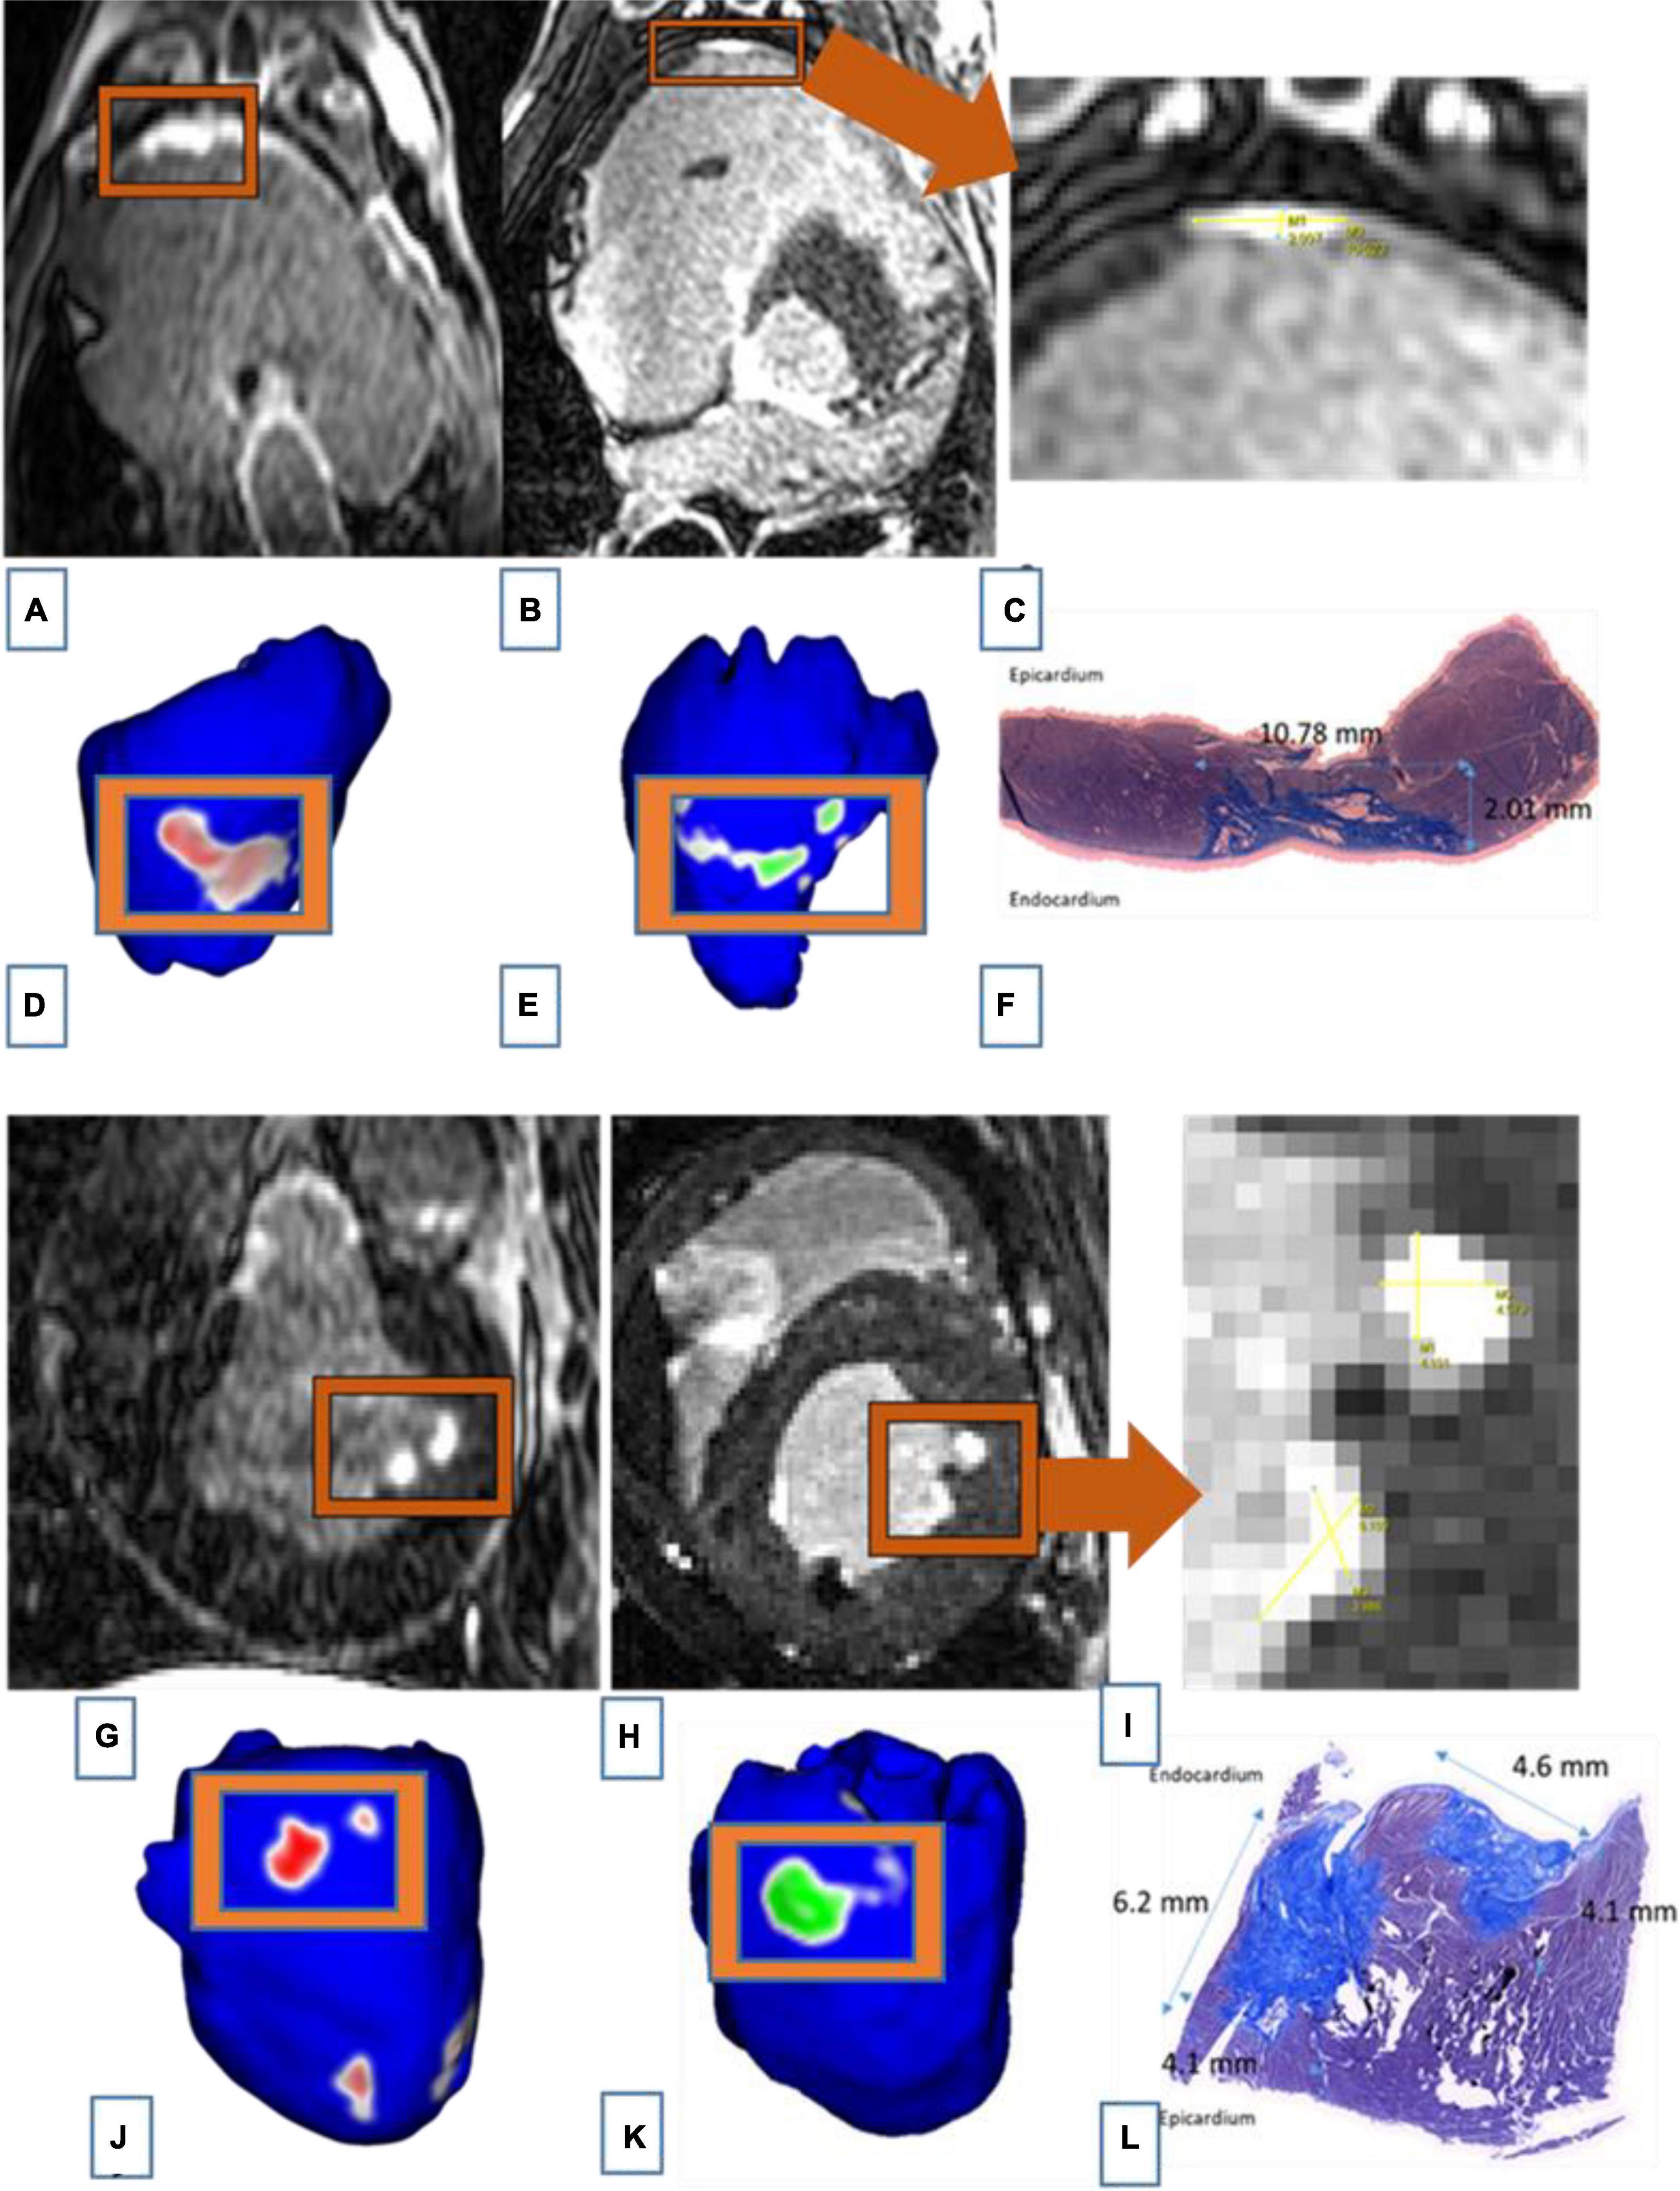

c- Comparison between LGE-MRI lesions and pathological assessment post necropsy

The similarity between LGE-MRI and pathological assessment can be seen in Figure 4. Maximal lesion depth and width seen on histology as compared to LGE-MRI are summarized in Table 2. There was no statistically significant difference between histological findings and LGE-MRI measurements (p = 0.973 for width; p = 0.741 for depth).

Figure 4. Images of two connected lesions in the RV free wall shown on LGE-MRI and corresponding Corview reconstructions in the acute phase [(A): axial view and (D)] and the chronic phase [(B): axial view and (E)]. Note the similarities between LGE-MRI in the chronic settings (B) and pathological assessment (F). Images of two unconnected lesions in the LV free wall shown on LGE-MRI and corresponding Corview reconstructions in the acute phase [(G): axial view and (J)] and the chronic phase [(H): axial view and (K)]. Note the similarities between LGE-MRI in the chronic settings (H) and pathological assessment (L). Images (C) and (I) are zoomed in figures of B and H, respectively.

Table 2. Comparison of acute and chronic lesion measurements obtained using LGE-MRI and histological assessment.

We also included Bland Altman Plots as a Supplementary Figure 1 to compare LGE-MRI and pathological assessment of lesions.

Magnetic Resonance Imaging-Histology Lesion Size Comparison

There was a strong correlation between lesions seen on LGE-MRI and lesions assessed by histology as shown in Figures 3, 4. We have shown that ventricular ablation lesion size defined by MRI can be reliably associated with lesion size demonstrated by histological analysis (18). Dickfield et al. used a canine model to show that both T1-weighted (T1w) and T2-weighted (T2w) images were reliable in defining right ventricular ablation lesion size as seen on histology 12 h after the procedure. Though the T2w images were more consistent and showed higher signal intensity for the central necrosis zone compared to their T1w counterparts (19). Furthermore, the studies of Breen et al. (20) and Kholmovski et al. (21) also support the dependability of MRI in defining ablation lesion size as validated by histological specimen analysis.

Using a porcine model, Harrison et al. (22) demonstrated that T2w images were accurate at predicting acute atrial lesion sizes but often overestimated chronic lesion volumes, as validated by histopathological sections. Ranjan et al. (23) also used a porcine model to show that LGE-MRI can help acutely identify gaps in ablation lesions, which was verified by pathology analysis of the atrial tissue. Future techniques need to be developed to precisely assess reliability of MRI in the acute settings. In fact, acute edema might be underestimated because of its resorption when sampling the tissue.